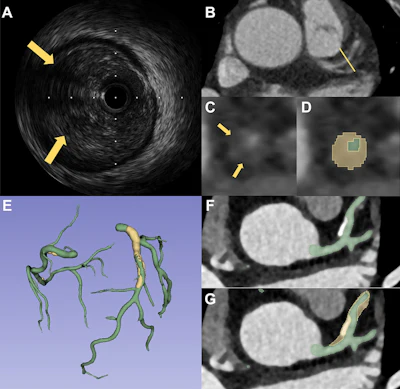

Two representative cases demonstrate the performance of PlaqueSegNet for coronary plaque segmentation. (A–D) Coronary CT angiography (CCTA) and intravascular US (IVUS) images in a 65-year-old male patient with chest pain for two months show plaque. (A) Cross-sectional IVUS image shows a lipid-rich plaque (hypoechoic, arrows). (B) Axial and (C) cross-sectional CCTA images show the same plaque (low-attenuation area, yellow line and arrows) in the proximal left anterior descending artery. (D) PlaqueSegNet segmentation of the noncalcified plaque (yellow shading) and coronary lumen (green shading) in the cross-sectional image. (E–G) CCTA images in a 57-year old female patient with chest pain for three months show multiple plaques. (E) Volume-rendered CCTA image of the coronary tree shows PlaqueSegNet plaque segmentation (yellow) in the right and left coronary arteries. (F, G) PlaqueSegNet segmentation delineates a mixed plaque (yellow shading) and coronary lumen (green shading) in the left main artery and proximal-to-mid left anterior descending artery.RSNA